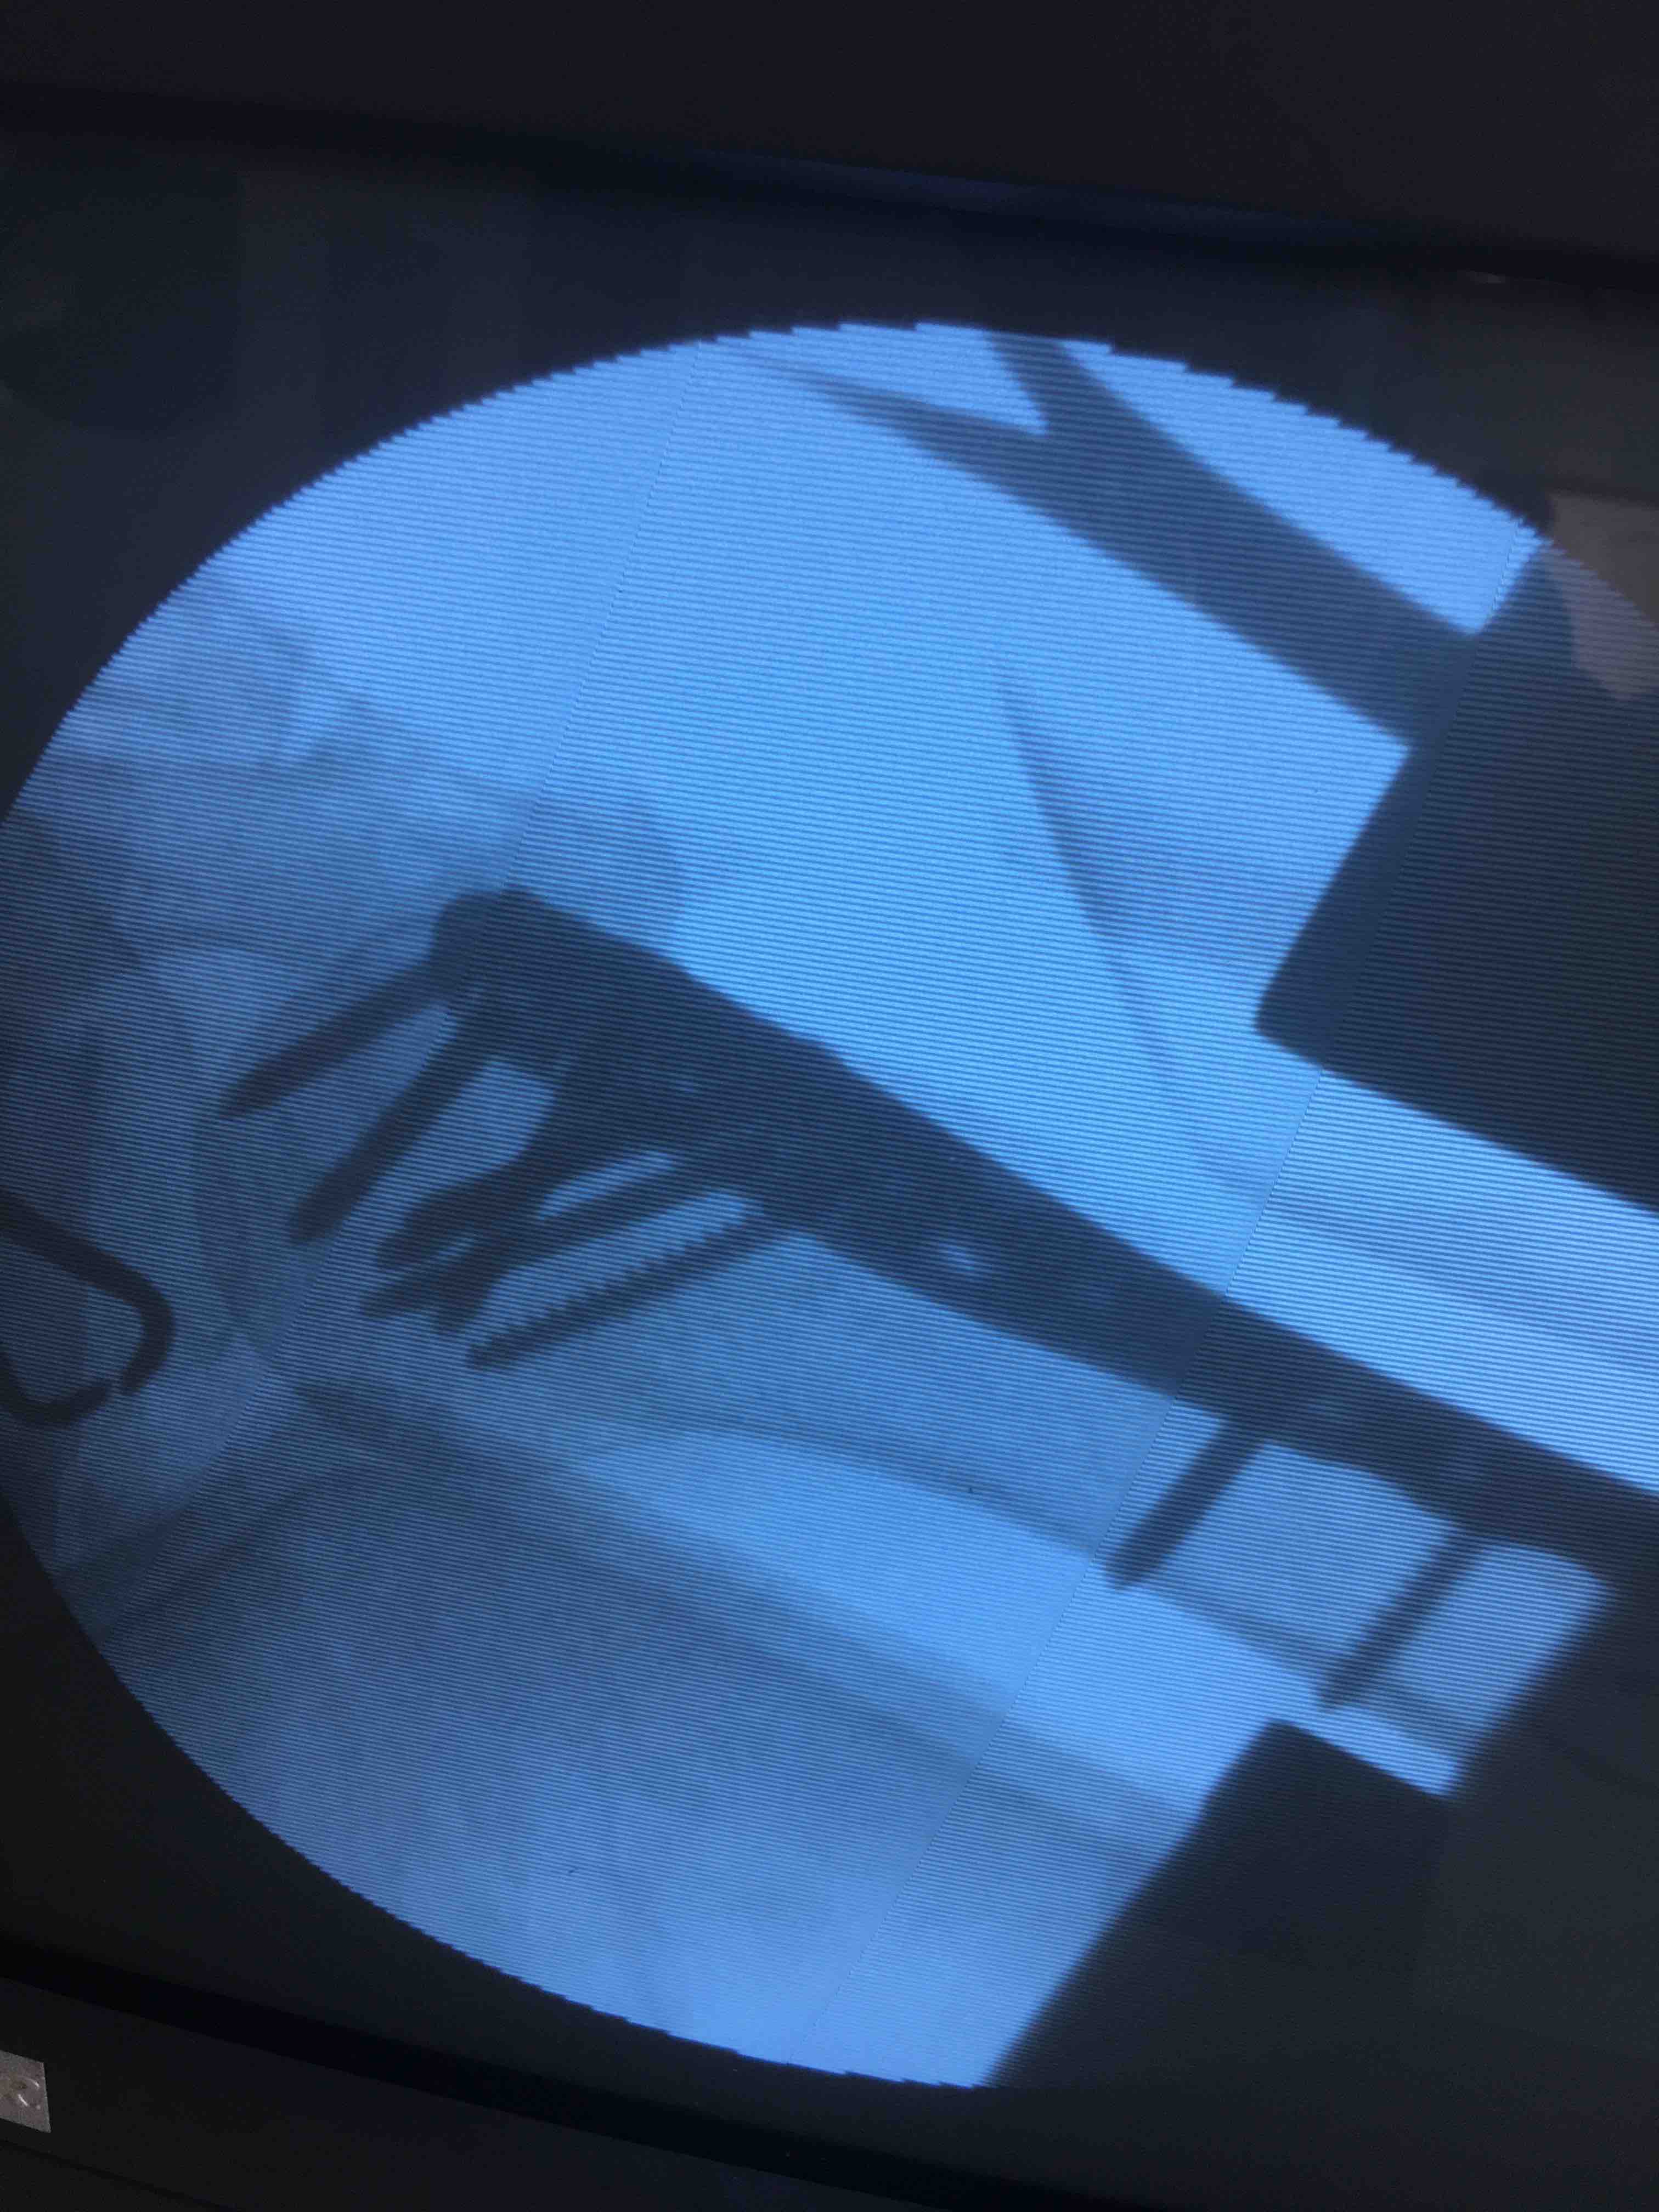

诊断右肱骨外科颈粉碎性骨折在臂丛麻醉下行切复内固定术,术后抗炎,消肿等处理。